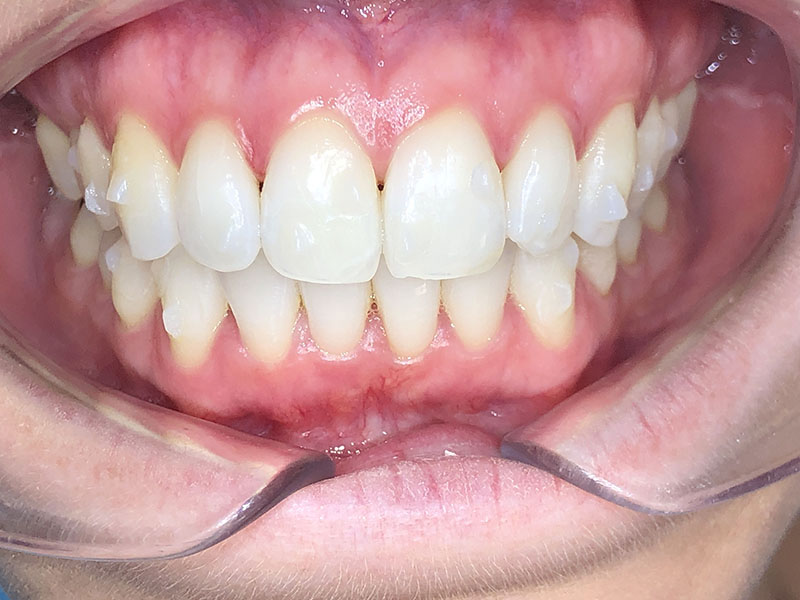

Patiente de 34 ans venue au cabinet pour une réhabilitation de son sourire suite à une récidive de son traitement d’orthodontie survenue pendant son adolescence, à cause du non-remplacement de sa contention perdue. Elle avait eu dans le passé une proposition de traitement par facettes pour réaliser l’alignement qu’elle avait refusé, ne voulant pas que l’on touche à ses dents.

À l’examen clinique, la patiente est en classe I d’Angle molaire bilatérale, indication idéale pour les traitements d’alignement simples que peuvent réaliser les omnipraticiens formés à cette thérapeutique.

Aucune autre pathologie ni problème dentaire ne furent relevés, en dehors d’un nettoyage préalable.